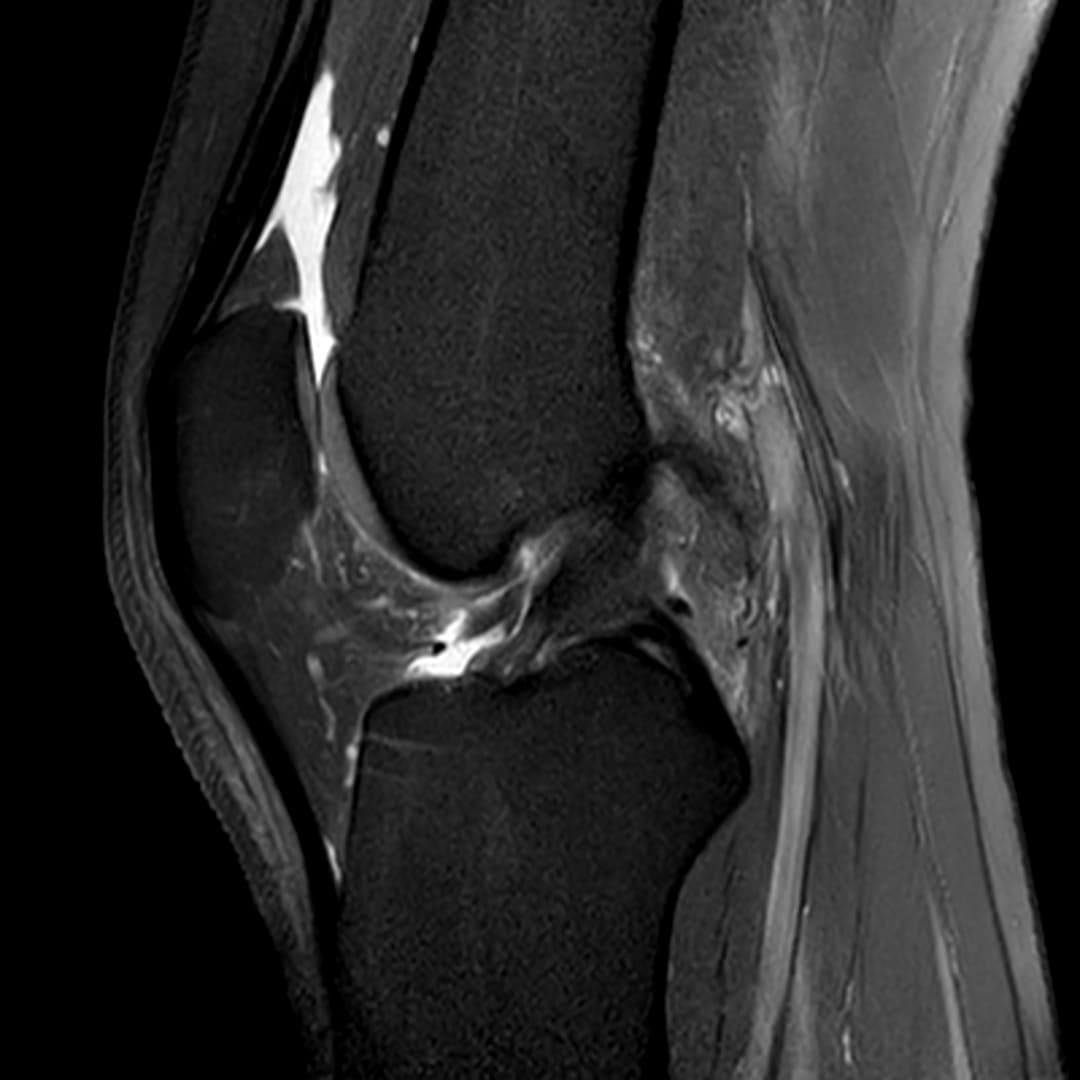

Languette méniscale rattachée à la corne antérieure du ménisque médial avec aspect flottant sur le versant antérieur de l'échancrure.